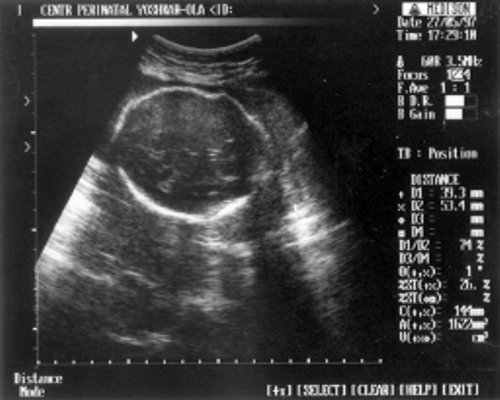

- Кости предплечья = 17,5 мм - 15,5 нед. (рис. 4)